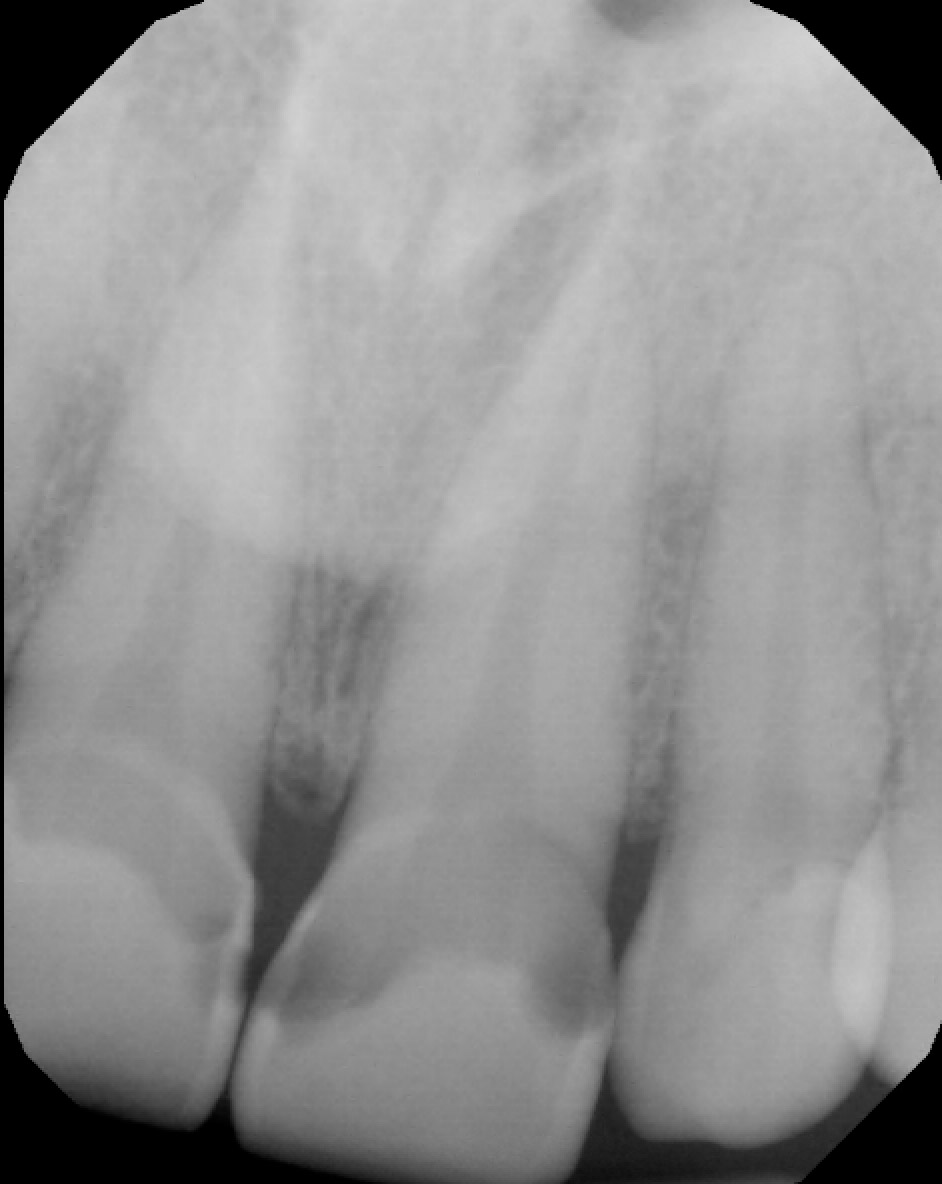

• Conclusion: The radiolucencies seen at the apex of 11 and 21 (US # 8 and 9) were not periapical lesions. I retook a PA with a different angle (see next slide)

• Additional radiographs

Note: No periapical lesion is noted on 11 and 21 (US # 8 and 9).